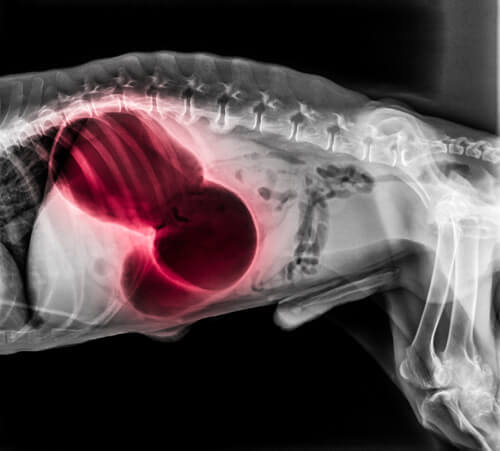

Wenn sich ein Blutgerinnsel, medizinisch Thrombus genannt, jedoch am falschen Ort oder aus dem falschen Grund bildet, kann es ein ernsthaftes Gesundheitsrisiko für deinen Hund darstellen.

Das Risiko besteht darin, dass ein Blutgerinnsel den Kreislauf des Körpers zum Erliegen bringen kann, wodurch die lebenswichtige Sauerstoffversorgung des Gewebes verhindert wird. Selbst wenn sich nicht sofort eine Verstopfung bildet, kann es zu wichtigen Organen wandern und Schäden verursachen.

Es ist wichtig, sich bewusst zu machen, dass ein Blutgerinnsel zum Beispiel einen Gehirnschlag und andere akute und lebensbedrohliche Zustände verursachen kann.